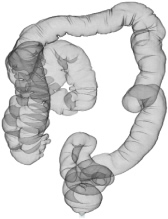

※大腸CT(仮想大腸内視鏡)

大腸CTは、内視鏡を使わない大腸検査です。大腸内視鏡と同様の前処置を行った後に、大腸を炭酸ガスによって拡張させ、新型のマルチスライスCT装置を用いて撮影することで大腸の3次元画像を簡単に得る検査です。

大腸CTは、仮想大腸内視鏡検査とも呼ばれ、内視鏡検査と比較して苦痛や違和感が少なく、短時間で検査可能で受診者の受容性が高いことから、これまで大腸の精密検査に抵抗感のあった方にもおすすめできる検査です。

• 大腸CT画像

• 3次元画像(仮想大腸内視鏡画像)